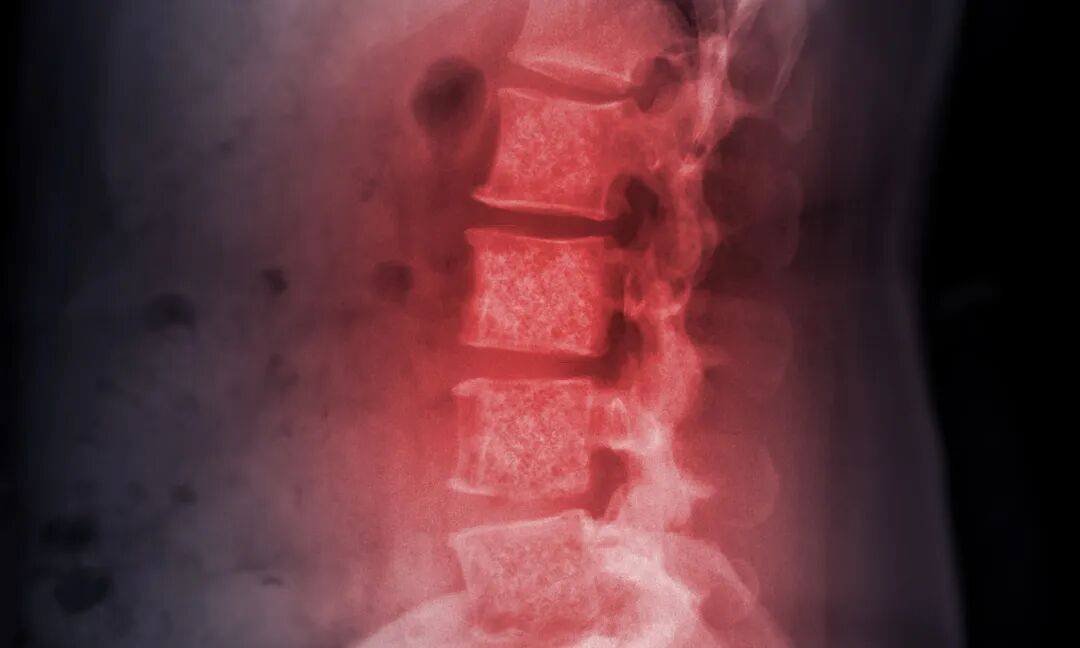

3. 骨骼

骨为肾之府,癌细胞易转移至脊柱、肋骨、四肢骨,常见于乳腺癌、肺癌、前列腺癌患者。转移后会出现剧烈骨痛、病理性骨折、肢体麻木,严重影响活动能力,中医认为是“肾虚骨弱、邪毒侵骨”所致。

图片